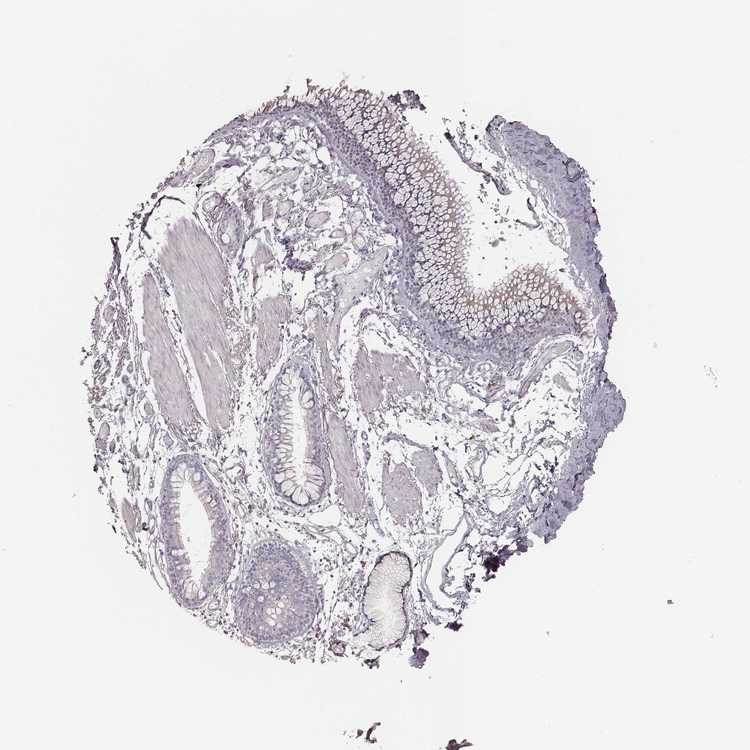

SOFT TISSUE 1 - Antibody stainingi

Antibody staining in the annotated cell types in the current human tissue is reported as not detected, low, medium, or high, based on conventional immunohistochemistry profiling in selected tissues. This score is based on the combination of the staining intensity and fraction of stained cells.

Each image is clickable and will lead to virtual microscopy that enables deeper exploration of all samples and also displays staining intensity scores, fraction scores and subcellular localization as well as patient and tissue information for each sample.

Antibody HPA035210Antibody HPA062272

Chondrocytes Not detected-

Fibroblasts -Not detected

SOFT TISSUE 2 - Antibody stainingi

Fibroblasts Not detectedNot detected

Peripheral nerve Not detectedNot detected